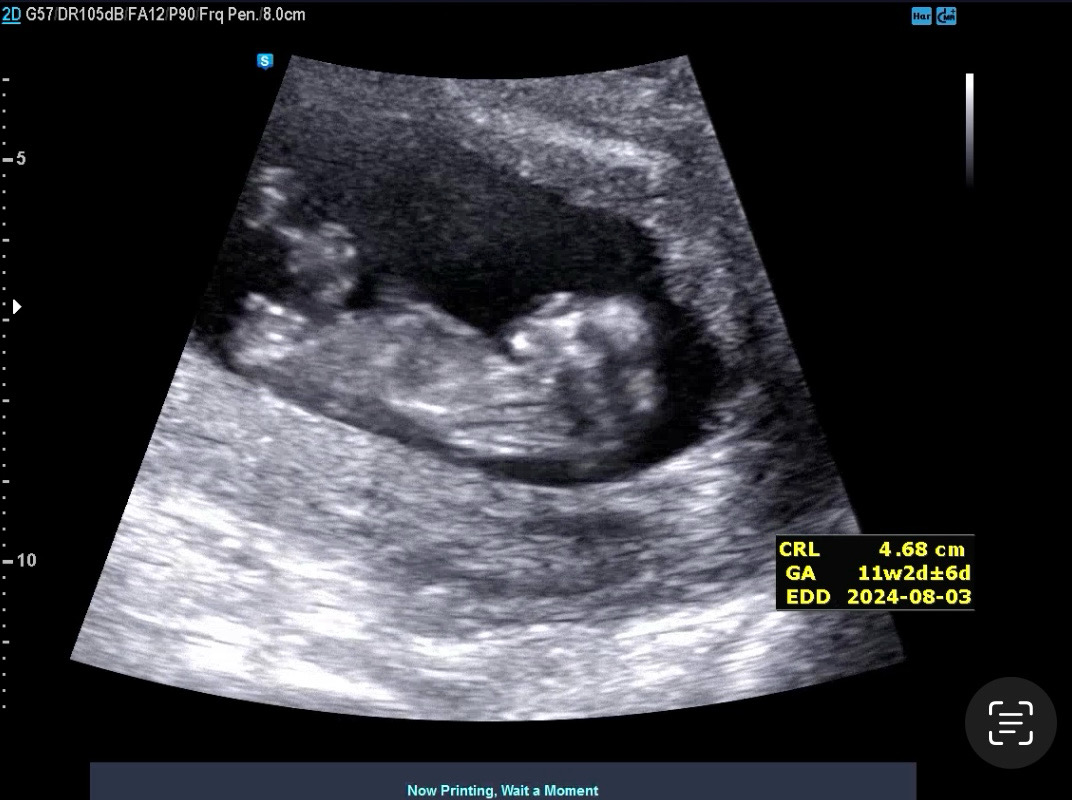

11주 각도법 문의드려요🤍

제 눈에 평행한 거 같은데 다른 베동맘들이 보시기엔 어떤가요??🤍

저두 평행해보여용~~조금 이르지만 🍑한표요

봐주셔서 너무 감사해요☺️ 🌶️여도 🍑여도 좋겠지만 그래도 딸이엇음 하는 마음이 더 크네용😂😂